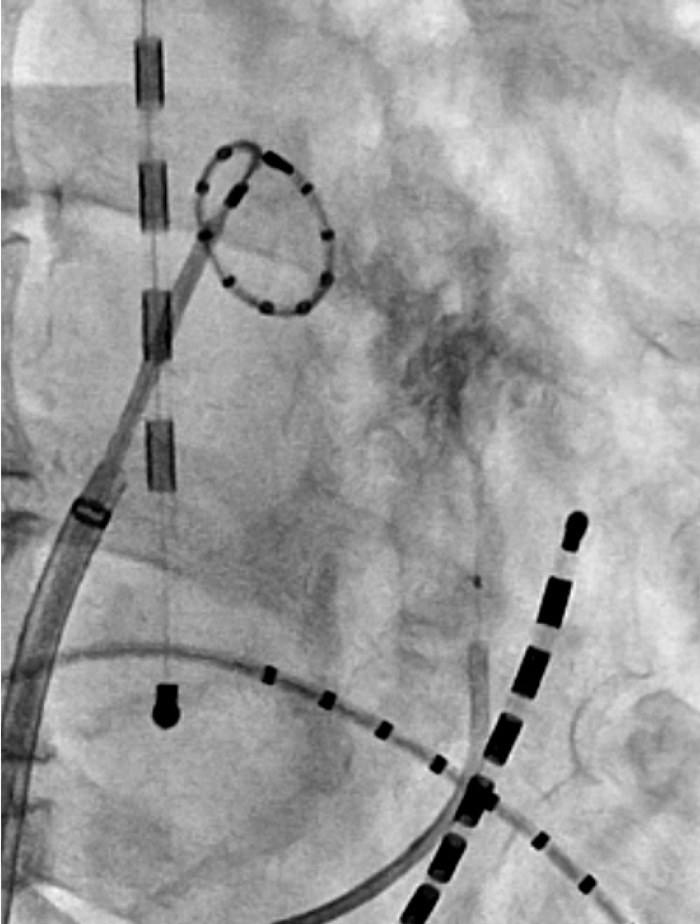

発作性心房細動に対しては従来の高周波を用いたアブレーション治療ではなく、主にクライオバルーンやレーザーバルーンを用いた、短時間で低リスクのアブレーション治療を行っています。特にレーザーによるアブレーションは心筋の深部まで到達するため、肺静脈の再伝導が少なく、心房細動の術後再発率が低下することが期待されています。

新たに次世代レーザーアブレーションの機器を2022年1月より導入いたしました。レーザーによりアブレーションは心筋深部まで焼灼することができるため、肺静脈の再伝導が少なく、心房細動の術後再発率が低くなることが期待されています。さらに2022年9月より最新のバルーンが使用可能となり、手術時間も短縮し、より安全で確実な手技ができるようになりました。当院は高知県で唯一のレーザーアブレーション導入施設です。当院では現在、発作性心房細動に対する第一選択のアブレーション法であり、全国で屈指の症例数を行っています。

発作性心房細動に対しては低リスクで短時間で終えることができるクライオバルーンアブレーションを行っています。肺静脈の形態によっては向かないケースもあります。持続性心房細動にも適応が拡大しており、必要と考えられるケースであれば肺静脈隔離に加えてクライオバルーンアブレーションでの左房後壁隔離も追加しています。

左肺静脈と左心耳の間を走行するマーシャル静脈へのエタノールアブレーションも行っています。静脈にエタノールを注入する化学的なアブレーション治療で、心臓の内側からの通常のアブレーションでは到達し難い部位へのアブレーションが可能です。実施できる施設は限られていますが、安全性および有効性が認められている治療法であり、有効性が期待できるケースで行っています。